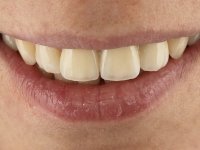

The surgical implant exposure and the healing screw placement proved to be a negative surprise regarding its position. Since the proposed removal of the implant was refused, we advanced to its provisional rehabilitation. An open tray impression technique was done, and a screwed abutment with a coronal and gingival component and an acrylic crown were made in the laboratory, using these two components. The provisional crown was placed in the mouth until a final decision was made. Six years passed before the patient returned to the clinic with an abscess on tooth 1.1. The choice to remove teeth 1.1 and 2.2 was made, to create a provisional 3-element bridge with a net to be adhered to the adjacent teeth. Surgery was planned and performed, placing the two implants at the site of 1.1 and 2.2, and the implant at the 2.1 site was cut with the objective of submerging it, while adequate tissue regeneration was performed (Surgical Work performed By Dr. Manuel Neves). During osseointegration, the patient used the fixed provisional bridge. A first impression was made for confection of a zirconia screwed provisional bridge, which worked the soft tissues for twelve weeks. The definitive impression was made with the individualisation of custom impression copings. Final rehabilitation was done with ceramized abutments, and also a bridge with zirconia infrastructure and ceramic cover. Due to the inclination of the implant placed at the site of tooth 1.1, the bridge required cemented fixation.